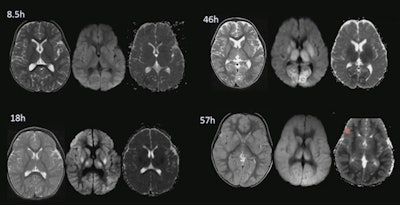

Before the use of hypothermia strategies, imagers attempted to find injuries and predict outcomes with diffusion in neonates. Even when diffusion and apparent diffusion coefficient (ADC) signs similar to stroke suggested that a child's brain was damaged, MR at five months follow-up would show normal signs where there had been diffusion abnormalities, Grant stated.

"We very quickly found out that diffusion wasn't always necrosis and that diffusion didn't always evolve to these areas of cystic encephalomalacia," Grant said.

Such decreased diffusion can be seen in inflammatory processes or transient metabolic compromise, so diffusion-weighted imaging (DWI) had to be understood in clinical context.

However, in neonates, DWI findings may not match the severity of injury, the latter being lesser or greater than the imaging suggests. Grant urged caution because delayed cell death can evolve over time in children.